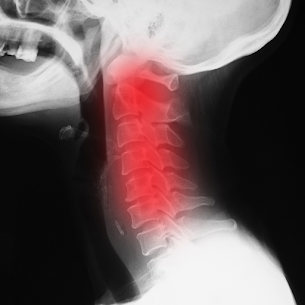

【ストレートネック(スマホ首)】 首や肩、背中の痛みはストレートネックが要因かもしれません 現代病と言われるストレートネックとなる原因に、スマホの使いすぎやPCデスクワーク、巻き肩や猫背などがあります。 酷くなると頭痛や眩暈、吐き気、肩こり、腕の痺れや冷えなど代謝不全の症状が出現します。...